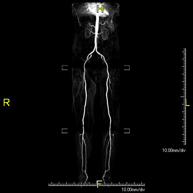

- Lower leg arterial MRI angiography

A non-invasive diagnostic screening that involves a vascular study of the aorto-iliac sector and the arterial vessels of both lower extremities, obtaining high-definition anatomical images using an electromagnetic field and radio waves (with transmitter and receiver). The use of paramagnetic contrast (gadolinium) is essential. However, it is a radiation-free procedure. The quality of the images allows for 2D and 3D reconstructions. It is particularly recommended for patients with suspected vascular disease in both extremities, patients with vascular disease in both extremities as a vascular map prior to treatment (percutaneous or surgical), as a pre-surgical vascular map in patients with bone or muscle injuries requiring surgery, etc.